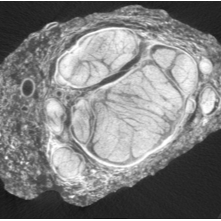

This protocol describes micro-computed tomography (microCT) imaging of an excised cadaveric human vagus nerve, stained appropriately, using SCANCO Medical equipment and software.

SR003-CR